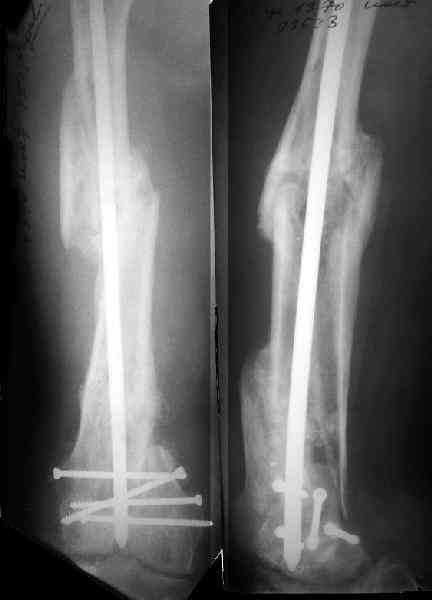

Это результат через полгода. К сожалению, пациент больше не приезжал на контрольный осмотр.